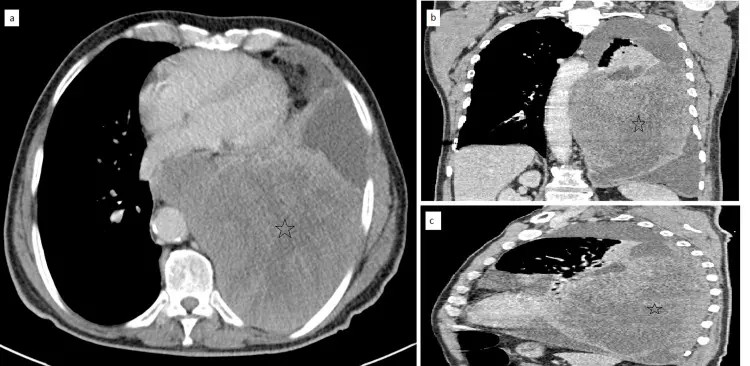

出典:Aichouni N, Kora C, Chbihi FZ, et al. Report of Two Pulmonary Sarcomatoïd Carcinoma Cases With Highlights on the Computed Tomography Features. Cureus. 2021;13(8):e16935.(CC BY 4.0)

まず胸部X線(レントゲン検査)や胸部CTで肺腫瘤の有無や大きさ、周囲組織への浸潤を確認します。必要に応じてPET-CTや頭部MRIなどを行い、リンパ節転移や遠隔転移の有無を評価して病期(ステージ)を決定します。